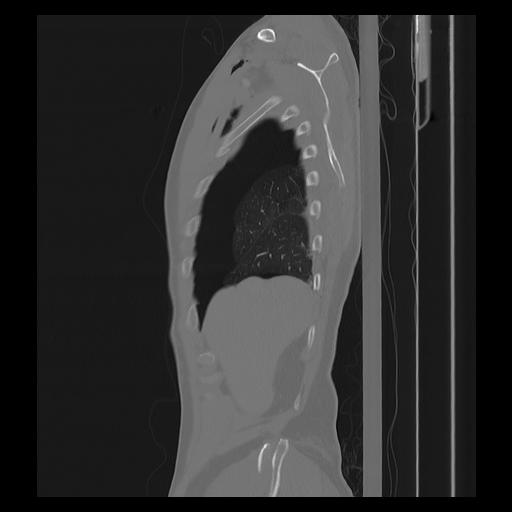

33 PULMON,CE,Sagittal,3.000,PULMON,Sagittal,